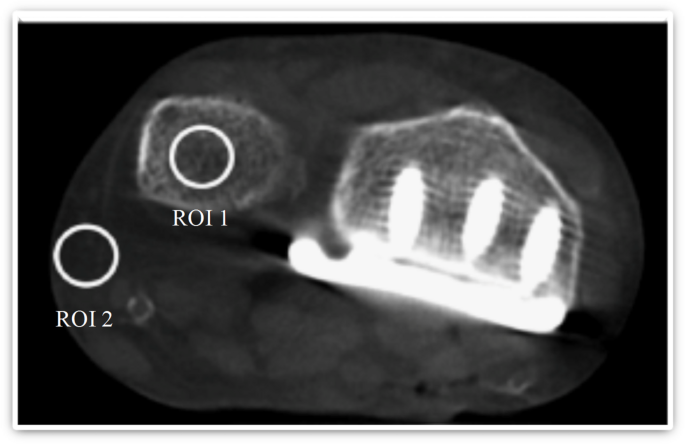

Objective image quality

Objective image analysis was performed on the distal ulna following placement of the radius plate. Signal-to-noise ratio (SNR) and contrast-to-noise ratio (CNR) were calculated using Hounsfield unit (HU) measurements from trabecular bone and subcutaneous fat. Regions of interest (ROIs) were consistently positioned according to a standardized protocol based on I. Yel, C. Booz, M. H. Albrecht et al.18, as demonstrated in Fig. 3. Each measurement was taken twice and averaged, with care taken to avoid artifacts. SNR and CNR were calculated using the following formulas19,20:

Representative axial image illustrating standardized regions of interest placed in trabecular bone (ROI 1) and subcutaneous fat (ROI 2) for objective image quality assessment. Regions of interest were defined to calculate signal-to-noise and contrast-to-noise ratios.

CBCT demonstrated significantly better performance in terms of image noise compared to MDCT (Fig. 5). The differences in signal-to-noise ratio (SNR, p = 0.0004) and contrast-to-noise ratio (CNR, p < 0.0001) were statistically significant. The SNR and CNR values for both imaging modalities are detailed in the subsequent Table 4.

Boxplot comparison of objective image quality metrics between CBCT and MDCT. Signal-to-noise ratio (SNR) and contrast-to-noise ratio (CNR) were calculated from defined ROIs in trabecular bone and subcutaneous fat.